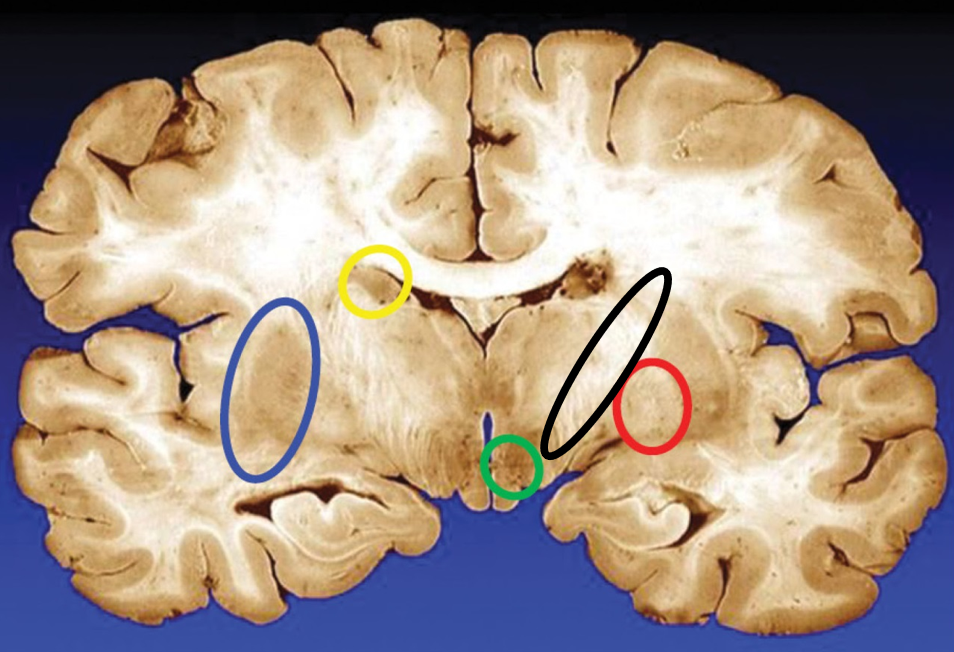

blue

putamen

yellow

caudate

green

subthalamic nuclei

black

internal capsule

red

globus pallidus

name the condition

Huntington’s (reduced caudate)